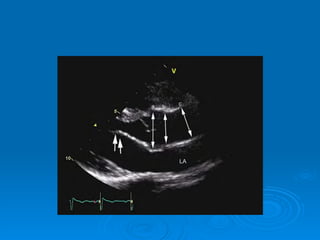

Echo-doppler Cardiaque Echographie bidimentionnelle: Épaississement de la valve Diminution d’ouverture valvulaire Aspect caractéristique en genou fléchi de la GVM Mesure de la surface mitrale Recherche de calcifications Recherche de thrombis intra auriculaire gauche Dilatation de OG Etude de l’appareil sous valvulaire

Echo-doppler Cardiaque Echographiebidimentionnelle: Épaississement de la valve Diminution d’ouverture valvulaire Aspect caractéristique en genou fléchi de la GVM Mesure de la surface mitrale Recherche de calcifications Recherche de thrombis intra auriculaire gauche Dilatation de OG Etude de l’appareil sous valvulaire